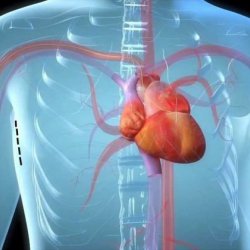

72 yaşındaki hastaya, açık kalp ameliyatının riskli olması nedeniyle Mersin'de ilk kez ameliyatsız kalp kapağı değişimi anlamına gelen Transkateter Aortik Kapak Implantasyonu (TAVI) yöntemi uygulandı. Solunum sıkıntısı ve kalp durması sorunu yaşayan …

72 yaşındaki hastaya, açık kalp ameliyatının riskli olması nedeniyle Mersin’de ilk kez ameliyatsız kalp kapağı değişimi anlamına gelen Transkateter Aortik Kapak Implantasyonu (TAVI) yöntemi uygulandı.